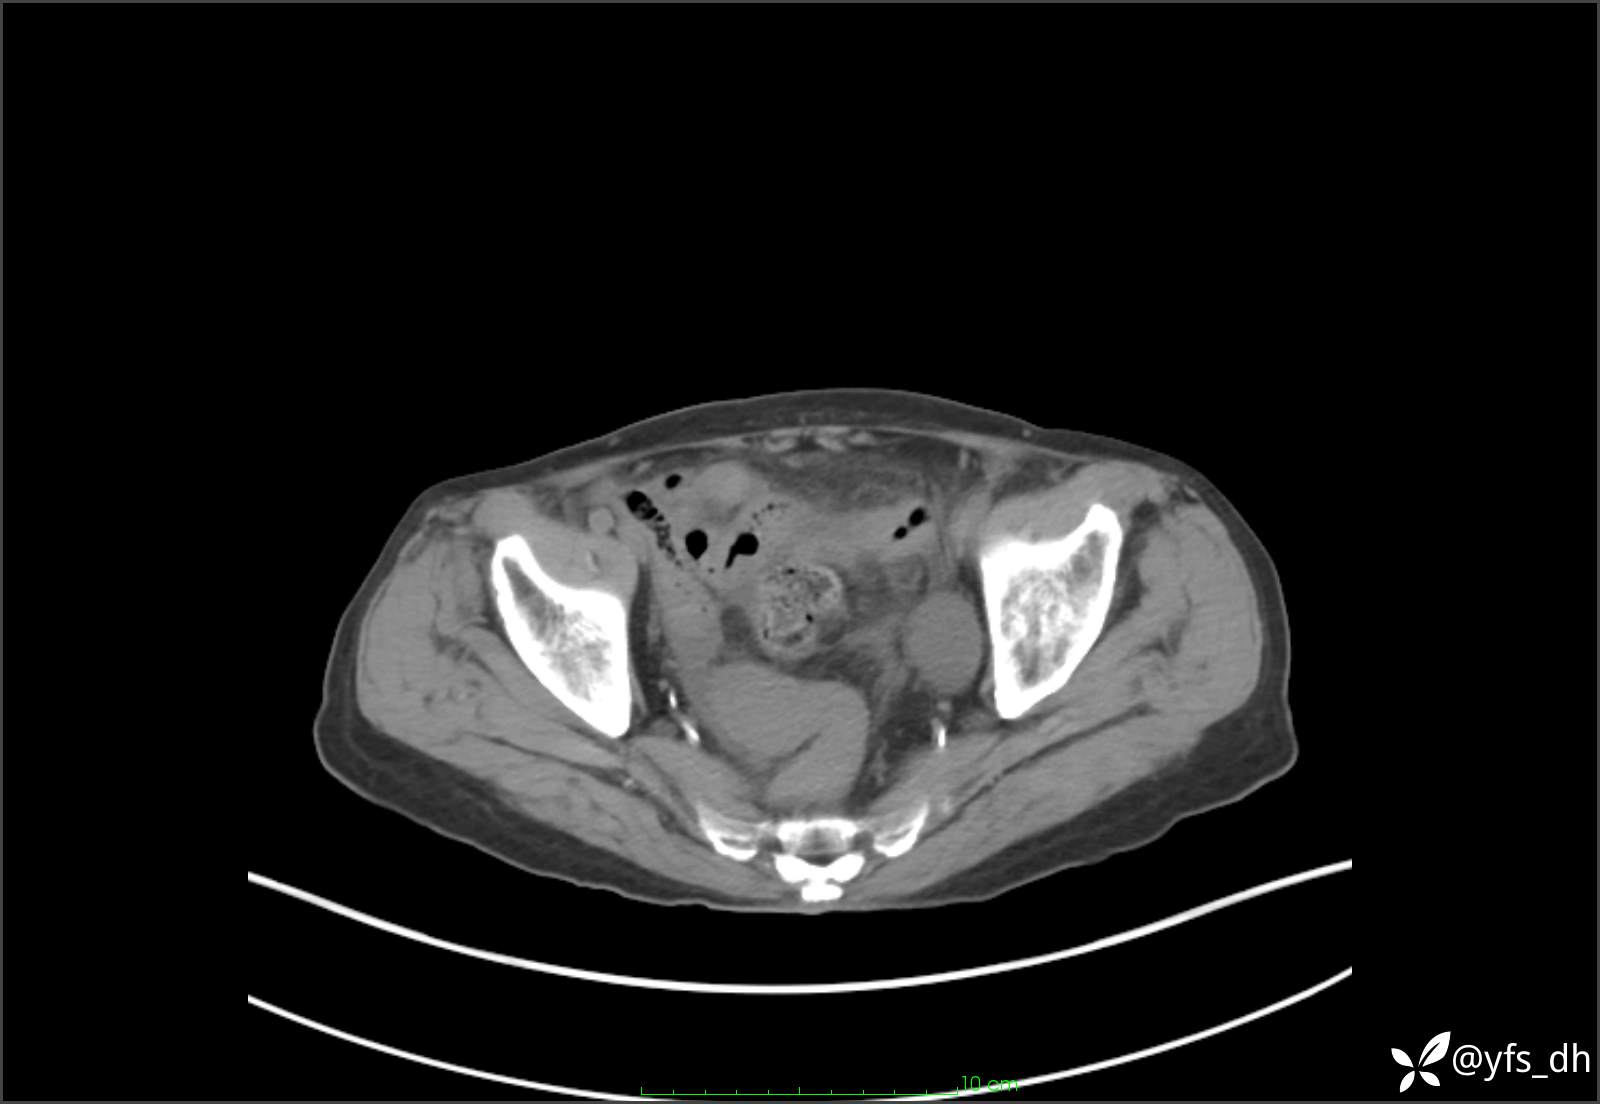

1.简要病史:患者4天前突发上腹部疼痛不适,但可以忍受。3小时前饭后突然加重,不能忍受后就诊。

2.简要手术记录:术中见腹盆腔大量肠液及粪便,乙状结肠中下段见一约3cm的破口。